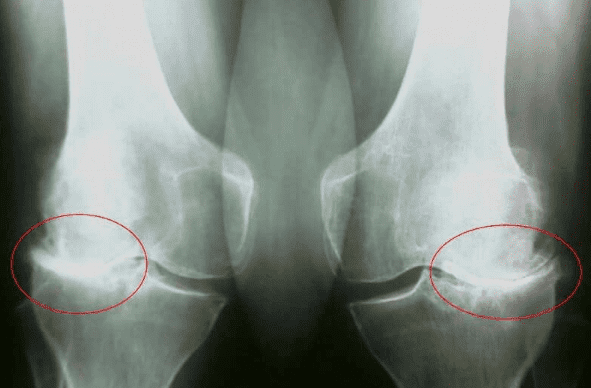

Lubomír Moravčík: Mám problém s kolenem, gonartrózu 3. stadia. Byla mi diagnostikována před pěti lety. Je to moje chyba, že jsem to ignoroval. Měl jsem začít s léčbou dříve, ale bral jsem jen léky proti bolesti, nemohl jsem přerušit trénink, je to moje práce. Nezáleží na tom, jak moc to bolí, musím být na fotbalovém hřišti, jinak zklamu celý tým.

Dr. Jan Pirk: Hlavními komplikacemi kloubních patologií jsou změny tvaru kloubu, silné omezení pohyblivosti a ankylóza, která kloub zcela znehybní a fixuje ho v často nesprávné poloze.

Při neúplném ohnutí a natažení kloubů se mění osy končetin, podél kterých se rozkládá hlavní mechanická zátěž těla. Kvůli systematickému porušování správné osy končetin se zvyšuje zátěž na ostatní klouby, což způsobuje sekundární degenerativní změny.

To je zvláště důležité u nosných kloubů: kolen, kyčlí, kotníků.

Osoba cítí VELMI SILNOU NESNESITELNOU BOLEST, kvalita života pacienta se zhoršuje: osoba se nemůže normálně pohybovat, nemůže vykonávat každodenní domácí práce, je nucena změnit zaměstnání, vzdát se svých koníčků a v 80 % případů se stává invalidní.